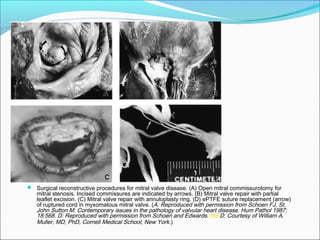

 Surgical reconstructive procedures for mitral valve disease. (A) Open mitral commissurotomy for

mitral stenosis. Incised commissures are indicated by arrows. (B) Mitral valve repair with partial

leaflet excision. (C) Mitral valve repair with annuloplasty ring. (D) ePTFE suture replacement (arrow)

of ruptured cord in myxomatous mitral valve. (A: Reproduced with permission from Schoen FJ, St.

John Sutton M: Contemporary issues in the pathology of valvular heart disease. Hum Pathol 1987;

18:568. D: Reproduced with permission from Schoen and Edwards.185 D: Courtesy of William A.

Muller, MD, PhD, Cornell Medical School, New York.)